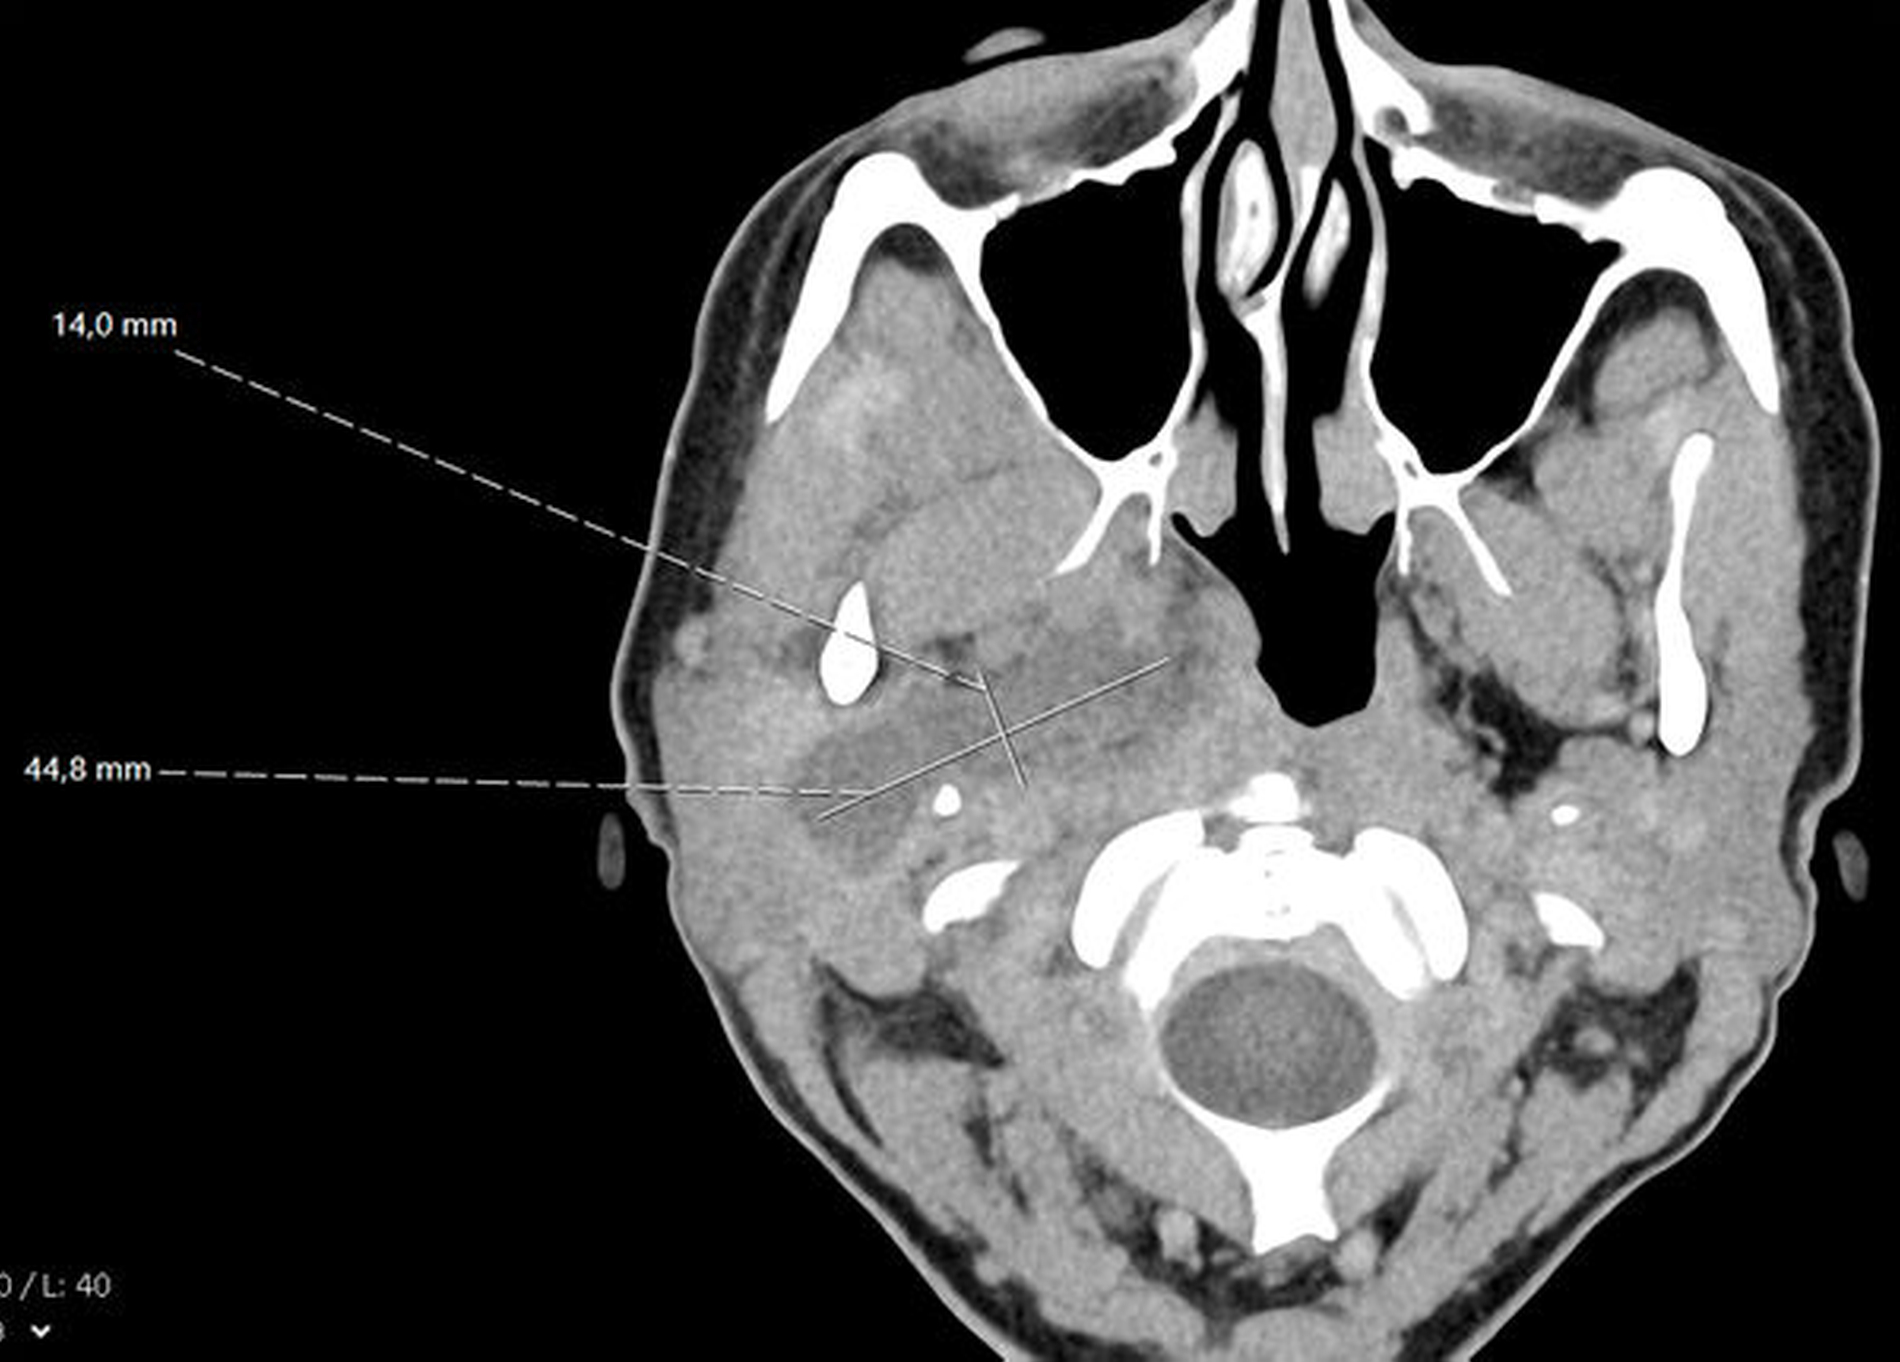

Sonografisch ließ sich weder von submandibulär noch von temporal eine klar abgrenzbare Abszessformation darstellen. Ein initial angefertigtes Labor zeigte stark erhöhte Entzündungsparameter mit einem C-reaktiven Protein von 261 mg/l (Normwert < 5 mg/l) sowie einer Leukozytose von 18/nl (Normwert 3,5–10/nl). Zur weiteren Diagnostik erfolgte die Anfertigung einer Computertomografie des Schädels mit Kontrastmittel. Hier zeigte sich eine circa 14 mm x 45 mm große, liquide Veränderung rechts im Musculus Pterygoideus mediales bis in die Glandula Parotis rechts reichend (Abbildungen 1 und 2). Aufgrund einer flauen Parenchymkontrastierung ließ sich eine Abszessformation nicht sicher ausschließen, die Befunde sprachen in Zusammenschau mit dem zeitlichen Ablauf und der stattgefundenen zahnärztlichen Behandlung jedoch in erster Linie für ein postinterventionelles Hämatom. Eine antikoagulatorische und/oder thrombozytenaggregatorische Therapie konnte ausgeschlossen werden.